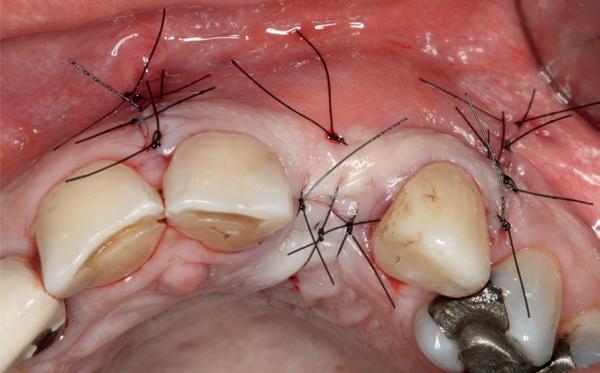

Na 4 weken intra-orale scan voor de etsbrug en kleurbepaling bij de technicus

• Plaatsen van de etsbrug met een composietcement

Voordat er gescand kon worden voor een etsbrug, werd een studiemodel vervaardigd om met de technicus te overleggen of er voldoende ruimte was voor 2 centrale incisieven in de mesio-distale zin en of er voldoende ruimte was in occlusie voor de vleugels van de etsbrug. Er hoeft enkel nog aan de 12 en 22 pala-

tinaal geslepen te worden als er geen 1,5 mm ruimte voor de vleugels behaald kan worden. De ruimte was op de dunste plekken 1 mm, dus een kleine preparatie in de 12 en 22 palatinaal was nodig. Omdat de kaak volledig afgevlakt was en dun was geworden, kunnen de dummies van de etsbrug enkel op de kaak “gelegd worden”, maar daarbij zijn er geen papillen en staat de cervicale rand van de dummies net voor de kaak. Een esthetisch resultaat kan daarmee niet behaald worden. Daarom is een aanvulling van de zachte weefsels in de breedte nodig, als het creëren van een emergence profile, waarbij het oogst alsof de gebitselementen uit het weefsel vertrekken.

pincisies met hechtingen naar het buccale en coronale deel getrokken en aldaar ingehecht. Met twee incisies werd ook de emergence profile gecreëerd (afbeelding 6-13). Voor een goede genezing van het

14. Direct postoperatief plaatsen

van de essix met 2 dummy tanden

15. Twee weken post operatief

16. Creëren van een duidelijke indeuking in de mucosa voor emergence profile

18. Etsbrug frontbeeld

19. Etsbrug palatinaal